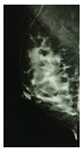

The PBD evaluated by the specialist for participant 1 is BI-RADS c for both breasts, and the outcome for the described clustering method is BI-RADS d and c for right and left breast, respectively. The CC mammography images for both breasts are presented in Figure 7, where the respective electrode ring positions are illustrated by the vertical yellow line. As it can be observed, there is a greater breast tissue in the plane covering the vertical yellow line of right breast than that corresponding to the left one. That is the reason why the resulting sectional PBD of right breast is greater than the left breast.

Figure 7. CC mammogram images of participant 1 and relative electrode ring position (yellow vertical line): (a) right breast; (b) left breast.